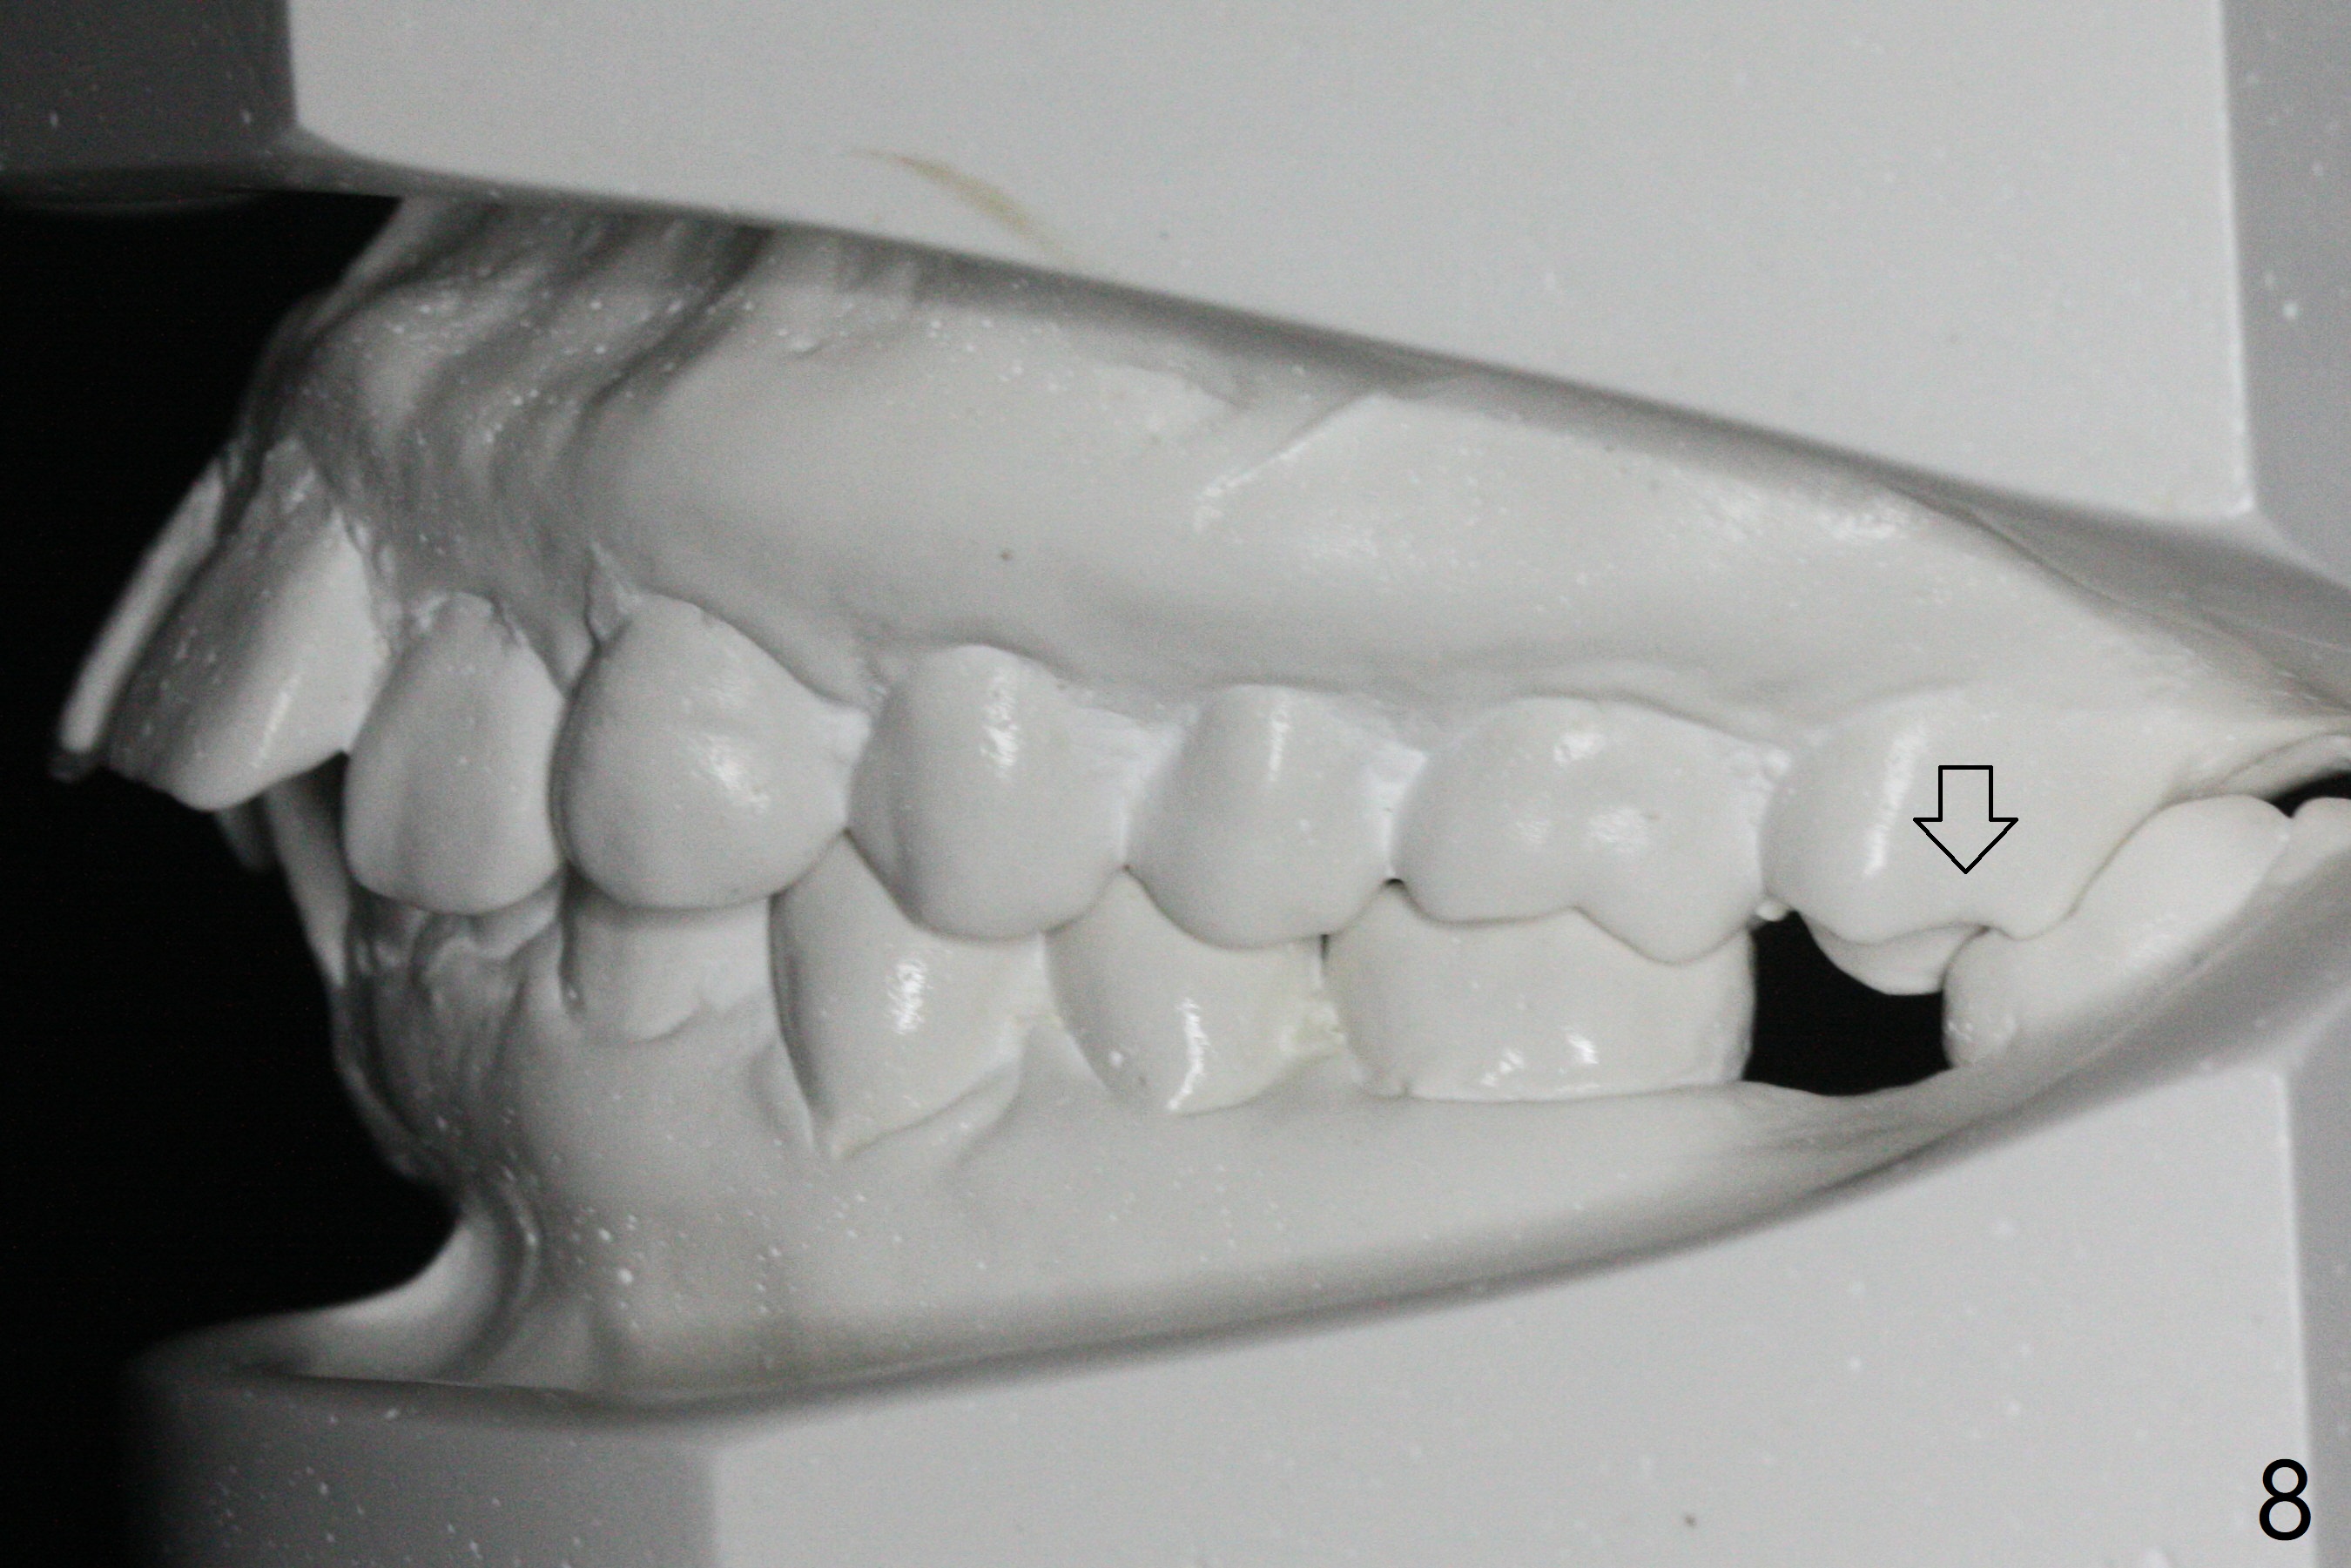

A 41-year-old woman requests ortho, bleach and replacement of 2 lower molars (L7s). The lips are protrusive (Fig.1,3), which is seemingly due to the underlying protrusive anterior teeth (Fig.4,5). Cephalometric tracing shows that SNA and SNB are both 87º (Fig.12), suggesting extraction. When the protrusive teeth are distalized, pay attention to move the upper dental midline to the right (Fig.2). BWs show subgingival calculus. SRP is required. Internal bleaching will be conducted for UL1 (Fig.7,11). Distalization is accomplished with extraction of 2 upper 1st bicuspids and using L8s as anchors so that no implants will be necessary for L7s. But the patient would rather have 2 of the lower 2nd molars for mastication. It appears that extraction of 4 bicuspids is pending (Fig.6-11). Supraeruption of U7s (Fig.6,8 arrows) will be corrected with banding.